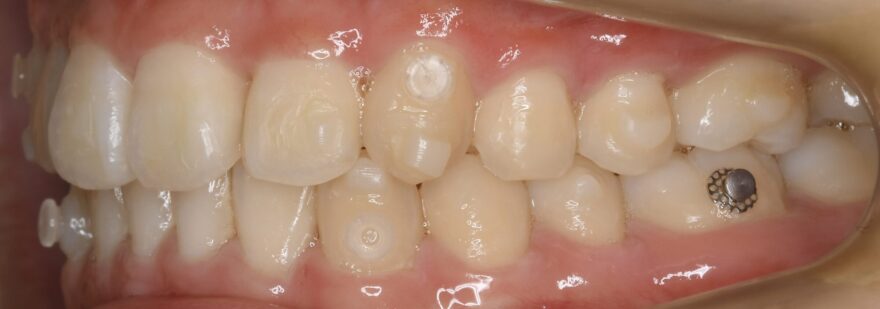

治療中の口腔内写真

インビザラインと他社製マウスピース矯正との違いにアタッチメントがあります。

歯の表面に付与する白くて小さい突起がアタッチメント。

アタッチメントとマウスピースが噛み合うことで、

・回転

・垂直移動

・水平移動

などといったマウスピース単体では苦手とされる、歯の3次元的な移動が可能となります。